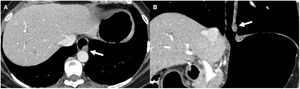

71-year-old man undergoing study for dysphagia, with a diagnosis of infiltrating lesion in the distal oesophagus by upper gastrointestinal endoscopy. Axial (A) and coronal (B) reconstructions of a Pneumo-CT with intravenous contrast, showing asymmetric mural thickening on the anterior wall of the distal oesophagus (arrow) and adjacent adenopathy (dotted arrow). C) Virtual endoscopy shows irregular reduction of the oesophageal lumen. D) Histology with haematoxylin and eosin staining (×100) showing atypical gland-forming epithelial proliferation consistent with adenocarcinoma.

Adenocarcinoma affects patients over 50 years of age. The most important risk factor is the presence of Barrett's oesophagus, a pre-malignant condition where the normal squamous epithelium of the lower part of the oesophagus is replaced by intestinal columnar epithelium.16,17 The most common location is the lower third of the oesophagus and it tends to invade the cardia and fundus by direct extension through the gastro-oesophageal junction. The most common symptoms include progressive dysphagia, odynophagia and weight loss; in the case of mediastinal invasion, there may be chest pain unrelated to swallowing.15 On Pneumo-CT, it usually presents as a diffuse thickening of the oesophageal wall, as a polypoid lesion with scalloped edges and irregularity of the mucosa, or as a mass that projects into the lumen of the oesophagus (Fig. 4).15